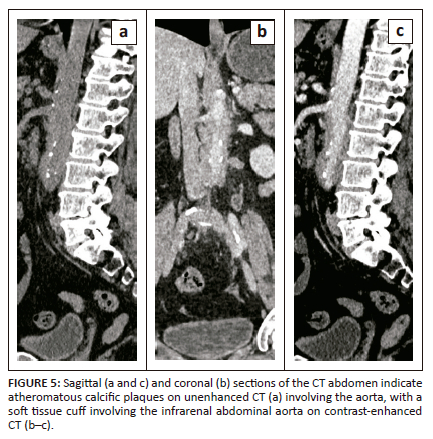

A 62-year-old female was referred for CECT of the abdomen for abdominal pain and unexplained weight loss. The study revealed a long circumferential cuff of soft tissue thickening involving the abdominal aorta starting at the level of the renal artery origin and extending for a length of 7.9 cm to the aortic bifurcation with a maximum single wall thickness of 14 mm. No other abnormality was noted at CT imaging (Figure 5a-c). Extensive blood serology for autoimmune vascular disorders revealed elevated IgG4 levels and erythrocyte sedimentation rate. The patient was started on therapy for IgG4-RD and symptoms improved drastically.